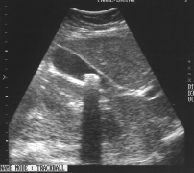

Эхограмма

желчного пузыря. В шейке желчного пузыря

визуализируется гиперэхогенная

структура до 1,5 см в диаметре (показана

стрелкой), дающая широкую акустическую

тень.